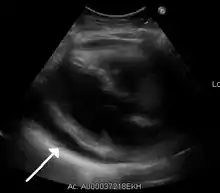

A 2D echo transthoracic echocardiogram of pericardial effusion. The "swinging" heart.

ECG: may present with sinus tachycardia, low voltage QRS as well as electrical alternans.[2] Due to the fluid accumulation around the heart, the heart is further away from the chest leads, which leads to the low voltage QRS. Electrical alternans signifies the up-and-down change of the QRS amplitude with every beat due to the heart swinging in the fluid (as displayed in the ultrasound image in the introduction) .[1] These three findings together should raise suspicion for impending hemodynamic instability associated with cardiac tamponade.

Echocardiogram (ultrasound): when pericardial effusion is suspected, echocardiography usually confirms the diagnosis and allows assessment of the size, location and signs of hemodynamic instability.[4] A transthoracic echocardiogram (TTE) is usually sufficient to evaluate pericardial effusion and it may also help distinguish pericardial effusion from pleural effusion and MI. Most pericardial effusions appear as an anechoic area (black or without an echo) between the visceral and the parietal membrane.[1] Complex or malignant effusions are more heterogeneous in appearance, meaning they may have variations in echo on ultrasound.[5] TTE can also differentiate pericardial effusion based on the size. Although it's difficult to define size classifications because they vary with institutions, most commonly they are as follows: small <10, moderate 10–20, large >20.[5] An echocardiogram is urgently needed for evaluation when there is concern for hemodynamic compromise, a rapidly developing effusion or history of recent cardiac surgery/procedures.[1]